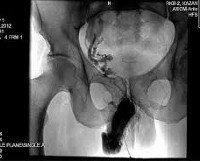

Кавернозография. Рентгенологическое исследование сосудов эрегированного полового члена с использованием контраста, введенного в кавернозное тело. Он позволяет получать информацию о состоянии венозной системы и кавернозных тел, выявлять сосуды, через которые осуществляется патологический отток крови, выявлять фиброзные бляшки, склероз или атрофию в кавернозном теле. Кавернозография является основным методом, используемым для дифференциальной диагностики артериогенной и веногенной эректильной дисфункции. Он используется для оценки важности различных патогенетических механизмов у пациентов с эректильной дисфункцией смешанного происхождения. Назначен на заключительном этапе обследования. Это может быть выполнено в амбулаторных или стационарных условиях. Не требует специальной подготовки.

Кавернозография - это классический метод ангиографии, используемый на последних этапах диагностики эректильной дисфункции. Содержит несколько изображений эрегированного полового члена, которые были записаны в динамике в разных проекциях. Кавернозография считается золотым стандартом в области дифференциальной диагностики и выявления причин эректильной дисфункции в сложных случаях. Точная оценка важности венозного компонента для развития эректильной дисфункции может значительно повысить эффективность лечения этой патологии. В дополнение к ультразвуковой визуализации полового члена и кавернозометрии, кавернозография включена в список обязательных диагностических процедур, необходимых для подозреваемой органической эректильной дисфункции. Это минимально инвазивный метод обследования. Гарантирует, что использование ионизирующего излучения назначается только при наличии достаточных доказательств.

Оценка результатов

Исследование позволяет определить причину эректильной дисфункции при потере вен и кавернозных тел полового члена. При обработке результатов кавернозографии, патологического венозного оттока, можно обнаружить наличие патологических шунтов между кавернозными телами и губчатым телом. Кроме того, каверноскопия позволяет выявить участки склероза и атрофии в кавернозных телах, вызванные предшествующими заболеваниями и травмами, фиброзными изменениями в оболочке кавернозных тел при болезни Пейрони и врожденными нарушениями структуры кавернозных тел или венозной сети полового члена. При травматических поражениях полового члена кавернозография указывает на наличие скопления контраста в зоне повреждения сосудов и кавернозных тел.

Отсутствие нарушений при кавероскопии указывает на артериальную природу органической эректильной дисфункции. Исключение психогенной эректильной дисфункции, как правило, не является необходимым, поскольку это выполняется на более ранней стадии дифференциальной диагностики. При эректильной дисфункции смешанного генеза кавернозные данные сравниваются с результатами других диагностических процедур (УЗИ полового члена, интракавернозный тест ), Что позволяет получить полную картину влияния нескольких патогенных механизмов на эректильную дисфункцию. терпеливые отношения.